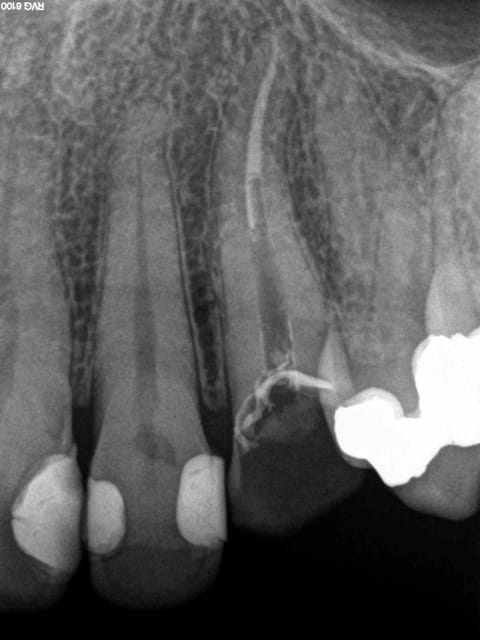

mon 3D kodak

un peu cherot effectivement mais revolutionne mon exercice en endo et évite les galères

un vision claire du nombre et de la disposition des canaux ainsi que de leur longueur réelle , je n'aurais jamais osé rêver çà ...

mon sterildent ... même s'il est controversé , depuis que je l'utilise je fonctionne en mode sans echec sur les dents porteuses d'infections apicales anciennes en retraitement